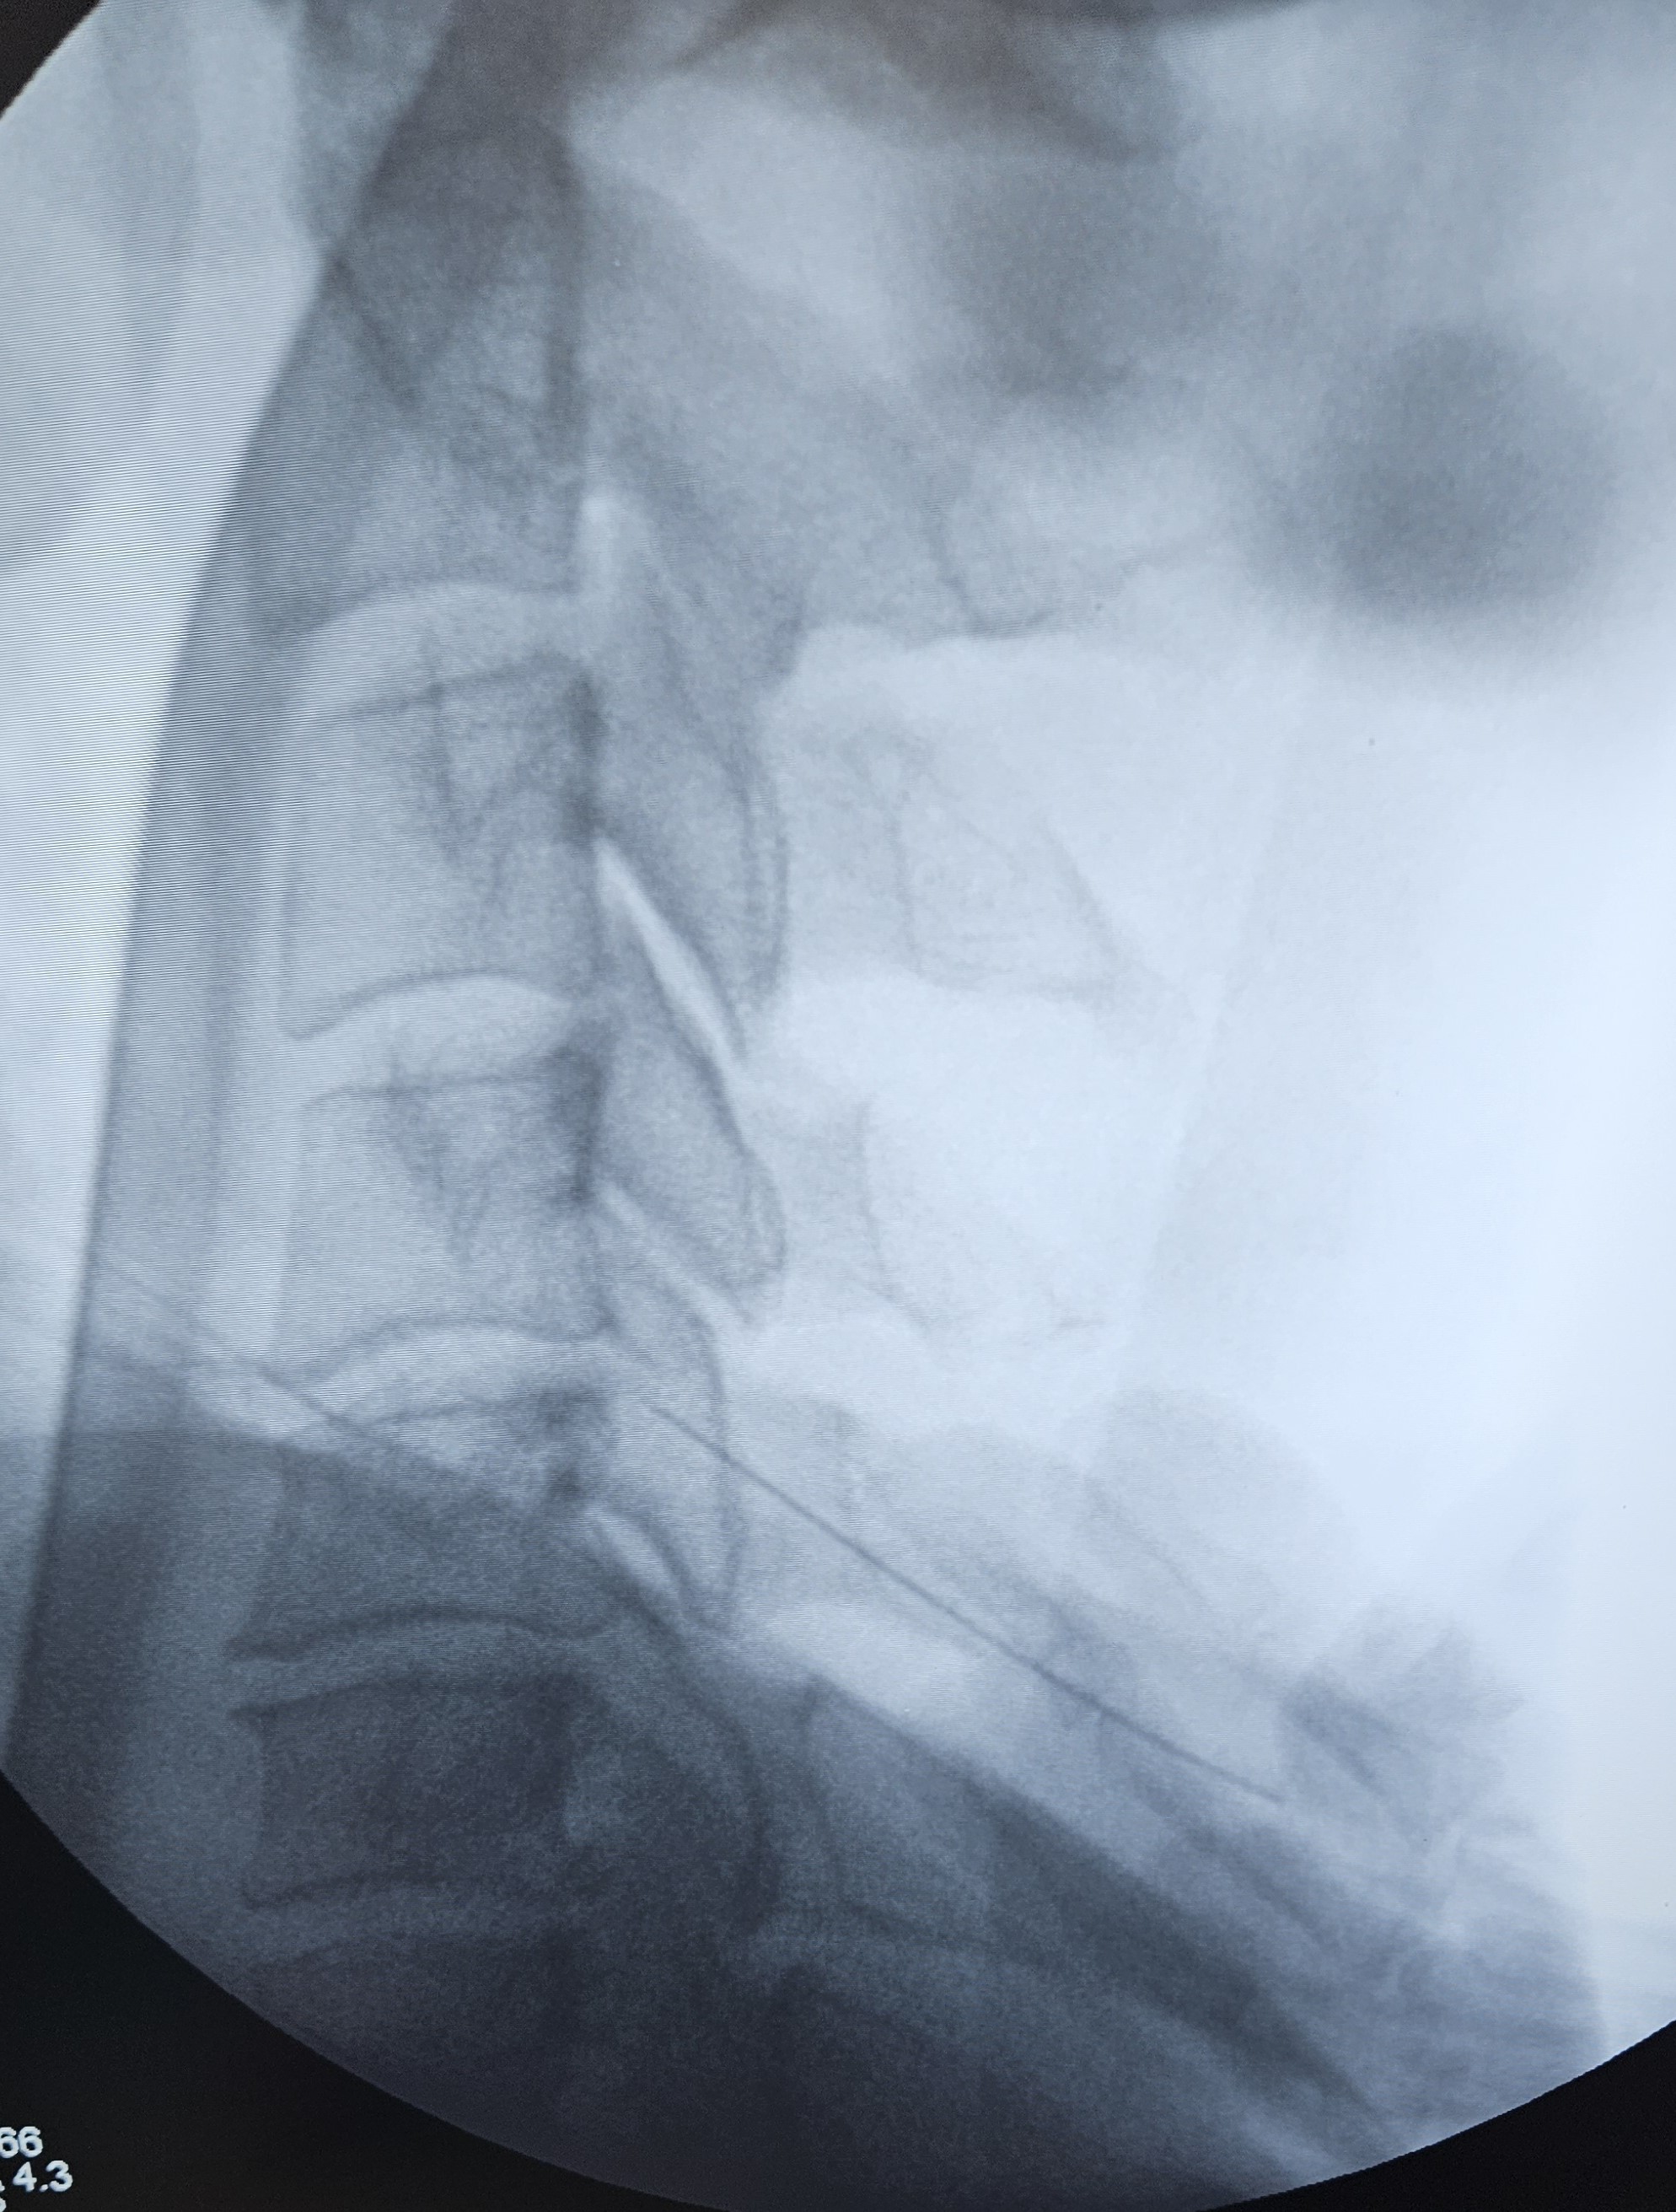

• Ενδοαρθρική έγχυση ή διαγνωστικός φαρμακευτικός νευρικός αποκλεισμός της άρθρωσης  προς επιβεβαίωση της πηγής του πόνου. Εάν υπάρξει άμεση ανακούφιση από τον πόνο, τότε η άρθρωση είναι πιθανώς η αιτία.

• Ενδοαρθρικές εγχύσεις κορτικοστεροειδούς υπό ακτινοσκοπικό έλεγχο

• Φαρμακευτικός νευρικός αποκλεισμός των μέσων νευρικών κλάδων που μεταφέρουν τα μηνύματα πόνου από την άρθρωση. Γίνεται με τη βοήθεια υπερήχου ή ακτινοσκοπικού

• Κατάλυση των μέσων νευρικών κλάδων με χρήση ραδιοσυχνοτήτων υπό ακτινοσκοπική καθοδήγηση

Με τον ασθενή σε πρηνή ή πλάγια κατακεκλιμένη θέση, χορηγείται τοπική αναισθησία για να μουδιάσει το δέρμα. Ο ιατρός εισάγει μια λεπτή βελόνα στο σημείο εντοπισμού των μέσων νευρικών κλάδων κάτω από ακτινοσκοπική καθοδήγηση. Ακολουθεί κινητικός και αισθητικός ερεθισμός και επί κατάλληλων ενδείξεων, η βελόνα συνδέεται με την πηγή ενέργειας, αφού εγχυθεί μικρή ποσότητα αναισθητικής ουσίας, για να μην δυσφορεί ο ασθενής κατά τη διάρκεια της παρέμβασης. Η ίδια διαδικασία ακολουθείται σε όλα τα επίπεδα που χρήζουν κατάλυσης.